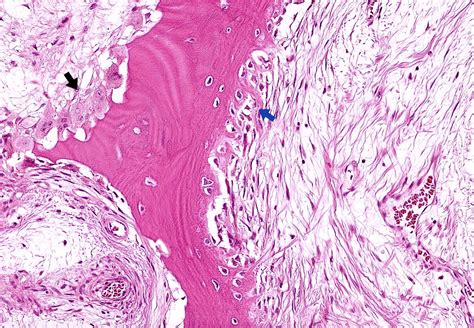

Pathology Outlines - Avascular necrosis

Pathology Outlines - Avascular necrosis